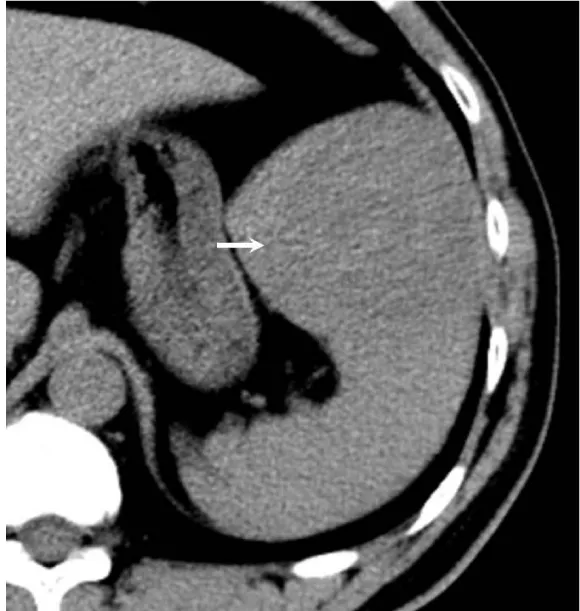

Solitary well-circumscribed masses were detected in all the five patients by ultrasound. One mass was of hypoecho, while the remaining masses were of hyperecho with posterior enhancement (Figure 1A). The maximum diameter ranged from 3.0 cm to 9.0 cm. At CT scanning, two masses appeared as hypodense (Figure 1B) and one was isodense (Figure 2A) to the normal spleenic parenchyma. In the two patients who received MR imaging, masses were isointensity at T1 weighted images (Figure 3A) and hypointensity with scattered sign void spots at T2 weighted images (Figure 3B). After intravenous injection of the contrast materials, all the five masses presented circle enhancement at arterial phase (Figure 3C and Figure 4A), while peripheral enhanced node was noted in one mass (Figure 2B). The circle enhancement persisted and radical line enhancement were observed at portal vein phase in 3 cases (Figure 1C) and progressive filling in was seen in two cases (Figure 2C). At delay phase of MR imaging, one lesion showed obvious enhancement with stellate low signal scar in the center comparing with surrounding splenic parenchyma (Figure 3D), while the other demonstrated central and circle enhancement to form a spoke-like appearance (Figure 4B). At delay enhanced CT scanning, two masses were isoattenuation to the surrounding splenic parenchyma (Figure 2D) and one lesion kept as hypoattenuation but with radial enhanced lines and enhanced circle to form a spoke-like appearance.

At pathological examination, all the masses were well demarcated on gross cut surface. A central stellate scar with peripheral interspersed dark brown nodules and the whitish intervening fibrous bands was noted to form spoke-like appearance (Figure 3E), which was well correlated with CT and MR imaging findings at enhancement. Microscopically, these angiomatoid nodules were surrounded by dense concentric collagen fibrous stroma and dispersed stromal cells with oval-to-spindle nuclei and scanty cytoplasm (Figure 3F). The abunden fibrous stroma may result in hypointensity at T2 weighted MR images. Hemosiderin was noted in the angiomatoid nodules (Figure 3G), which might contributed to signal void at T2 weighted MR images.

It usually affects middle-aged adults [6] and it is commonly found incidentally on radiographic imaging, or during operation for an unrelated condition. In present series, the patients are middle-aged adults without any related symptoms and the lesions were detected incidentally at routine ultrasound of health examinations. On ultrasound, manifestations of SANTs are vary widely from heterogeneous echo-texture with hyperechogenic, hypoechogenic, or isoechogenic appearing lesions, which are unspecific [7,8]. CT and MRI can show some characteristic features of SANTs, which include a solitary well demarcated mass with early peripheral enhancemant with radiating lines and progressive enhancement at the delay phase, and hypointens at T2 weighted MR images [2,3,5,9-13]. These features reflect the underlying pathological changes of scattered angiomatoid nodules separated and surrounded by sclerotic fibrotic stroma [10]. In present series, we also observed these characteristic features with well correlation to pathological findings. Circle and spoke-like enhancement can be contributed to fibrotic stroma surrounding and separating the angiomatoid nodules. The sclerotic fibrotic stroma may also result in isodense on CT, isointensity on T1 weighted images and hypointensity on T2 weighted images of MR imaging. The signal void spots at T2 weighted MR images have not been described at other literatures and may be contributed to hemosiderin deposition due to magnetic susceptibilty artifact.